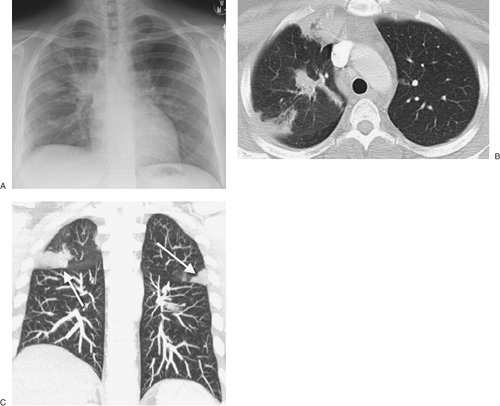

FIGURE 12-7. Chronic eosinophilic pneumonia. A: PA chest radiograph of a 30-year-old woman with several months' history of productive cough, fever, fatigue, chills, and dyspnea on exertion, treated unsuccessfully with several courses of antibiotics, shows bilateral ill-defined opacities, predominantly in the mid lungs. B: CT shows peripheral and central airspace disease. C: CT coronal reformatted image clearly shows the subpleural, peripheral distribution of disease (arrows). The patient improved rapidly with steroid treatment.

Chronic EP is most prevalent in the third to seventh decades of life, with women outnumbering men by 2 to 1 (10). Symptoms of dyspnea, cough, wheeze, malaise, weight loss, fever, and night sweats can be mild or severe. Blood eosinophilia occurs in the majority of patients. Serum IgE is normal or only mildly elevated, which is helpful in distinguishing the condition from allergic bronchopulmonary aspergillosis and tropical and parasitic pulmonary eosinophilias, in which serum IgE levels are markedly elevated. The classic findings on chest radiograph and CT are nonspecific peripheral, nonsegmental, homogeneous alveolar opacities, often with air bronchograms (10,11) (Figs. 12-5 and 12-6). In a minority of patients, the opacities are central in distribution or both central and peripheral (Fig. 12-7). Chronic EP is sensitive to steroid therapy; rapid clearing of radiologic abnormalities is usually seen within a few days, with complete clearing by 1 month. Relapse is common, and the majority of patients need long-term low-dose steroids, distinguishing this disease from acute EP (12). The radiologic manifestations can be migratory, occurring in new locations with relapse.

Radiographs and CT scans of the chest resemble those of many other types of pneumonia and show bilateral, patchy, nonsegmental, airspace opacities with a peripheral and basilar predominance (18). The opacities may contain air bronchograms. On occasion, the opacities are not peripheral in distribution but are central and centered along bronchovascular bundles. Although COP is usually a bilateral process, occasionally only one lung is involved or is much more involved than the other lung (Fig. 12-13). Areas of ground-glass attenuation are common and may be the only finding on CT.